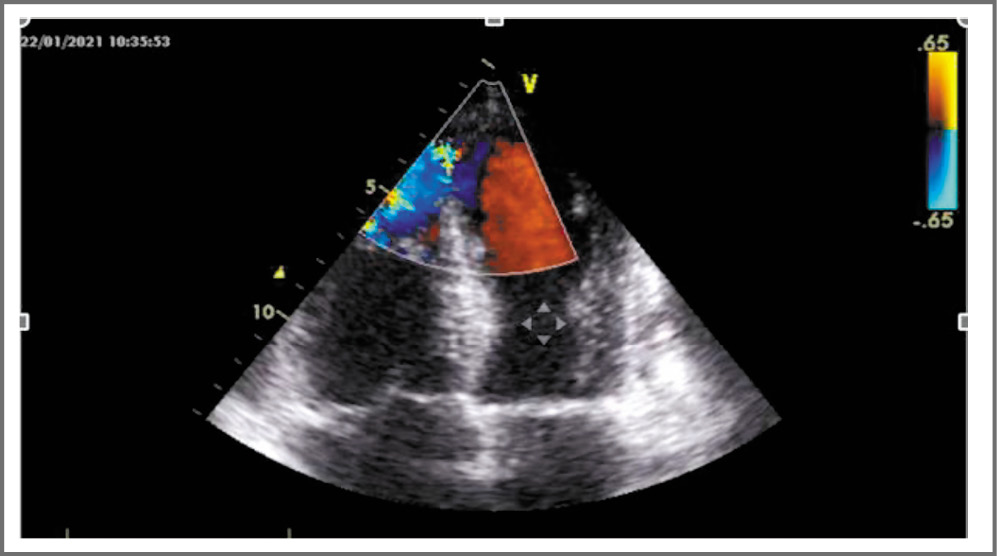

На следующий день выполнена ЭхоКГ, при которой впервые выявлен дефект МЖП в области верхушки диаметром 13 мм со сбросом крови слева направо (рис. 3). Фракция выброса левого желудочка – 42,4%, акинез верхушечных сегментов всех стенок.

Рис. 3. Дефект МЖП по данным ЭхоКГ в четырехкамерной позиции.